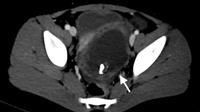

CT scan of a young girl presenting with ovarian torsion. The large pelvic cystic lesion contains calcifications (white arrow) consistent with a teratoma or dermoid cyst

From the collection of Dr KuoJen Tsao; used with permission